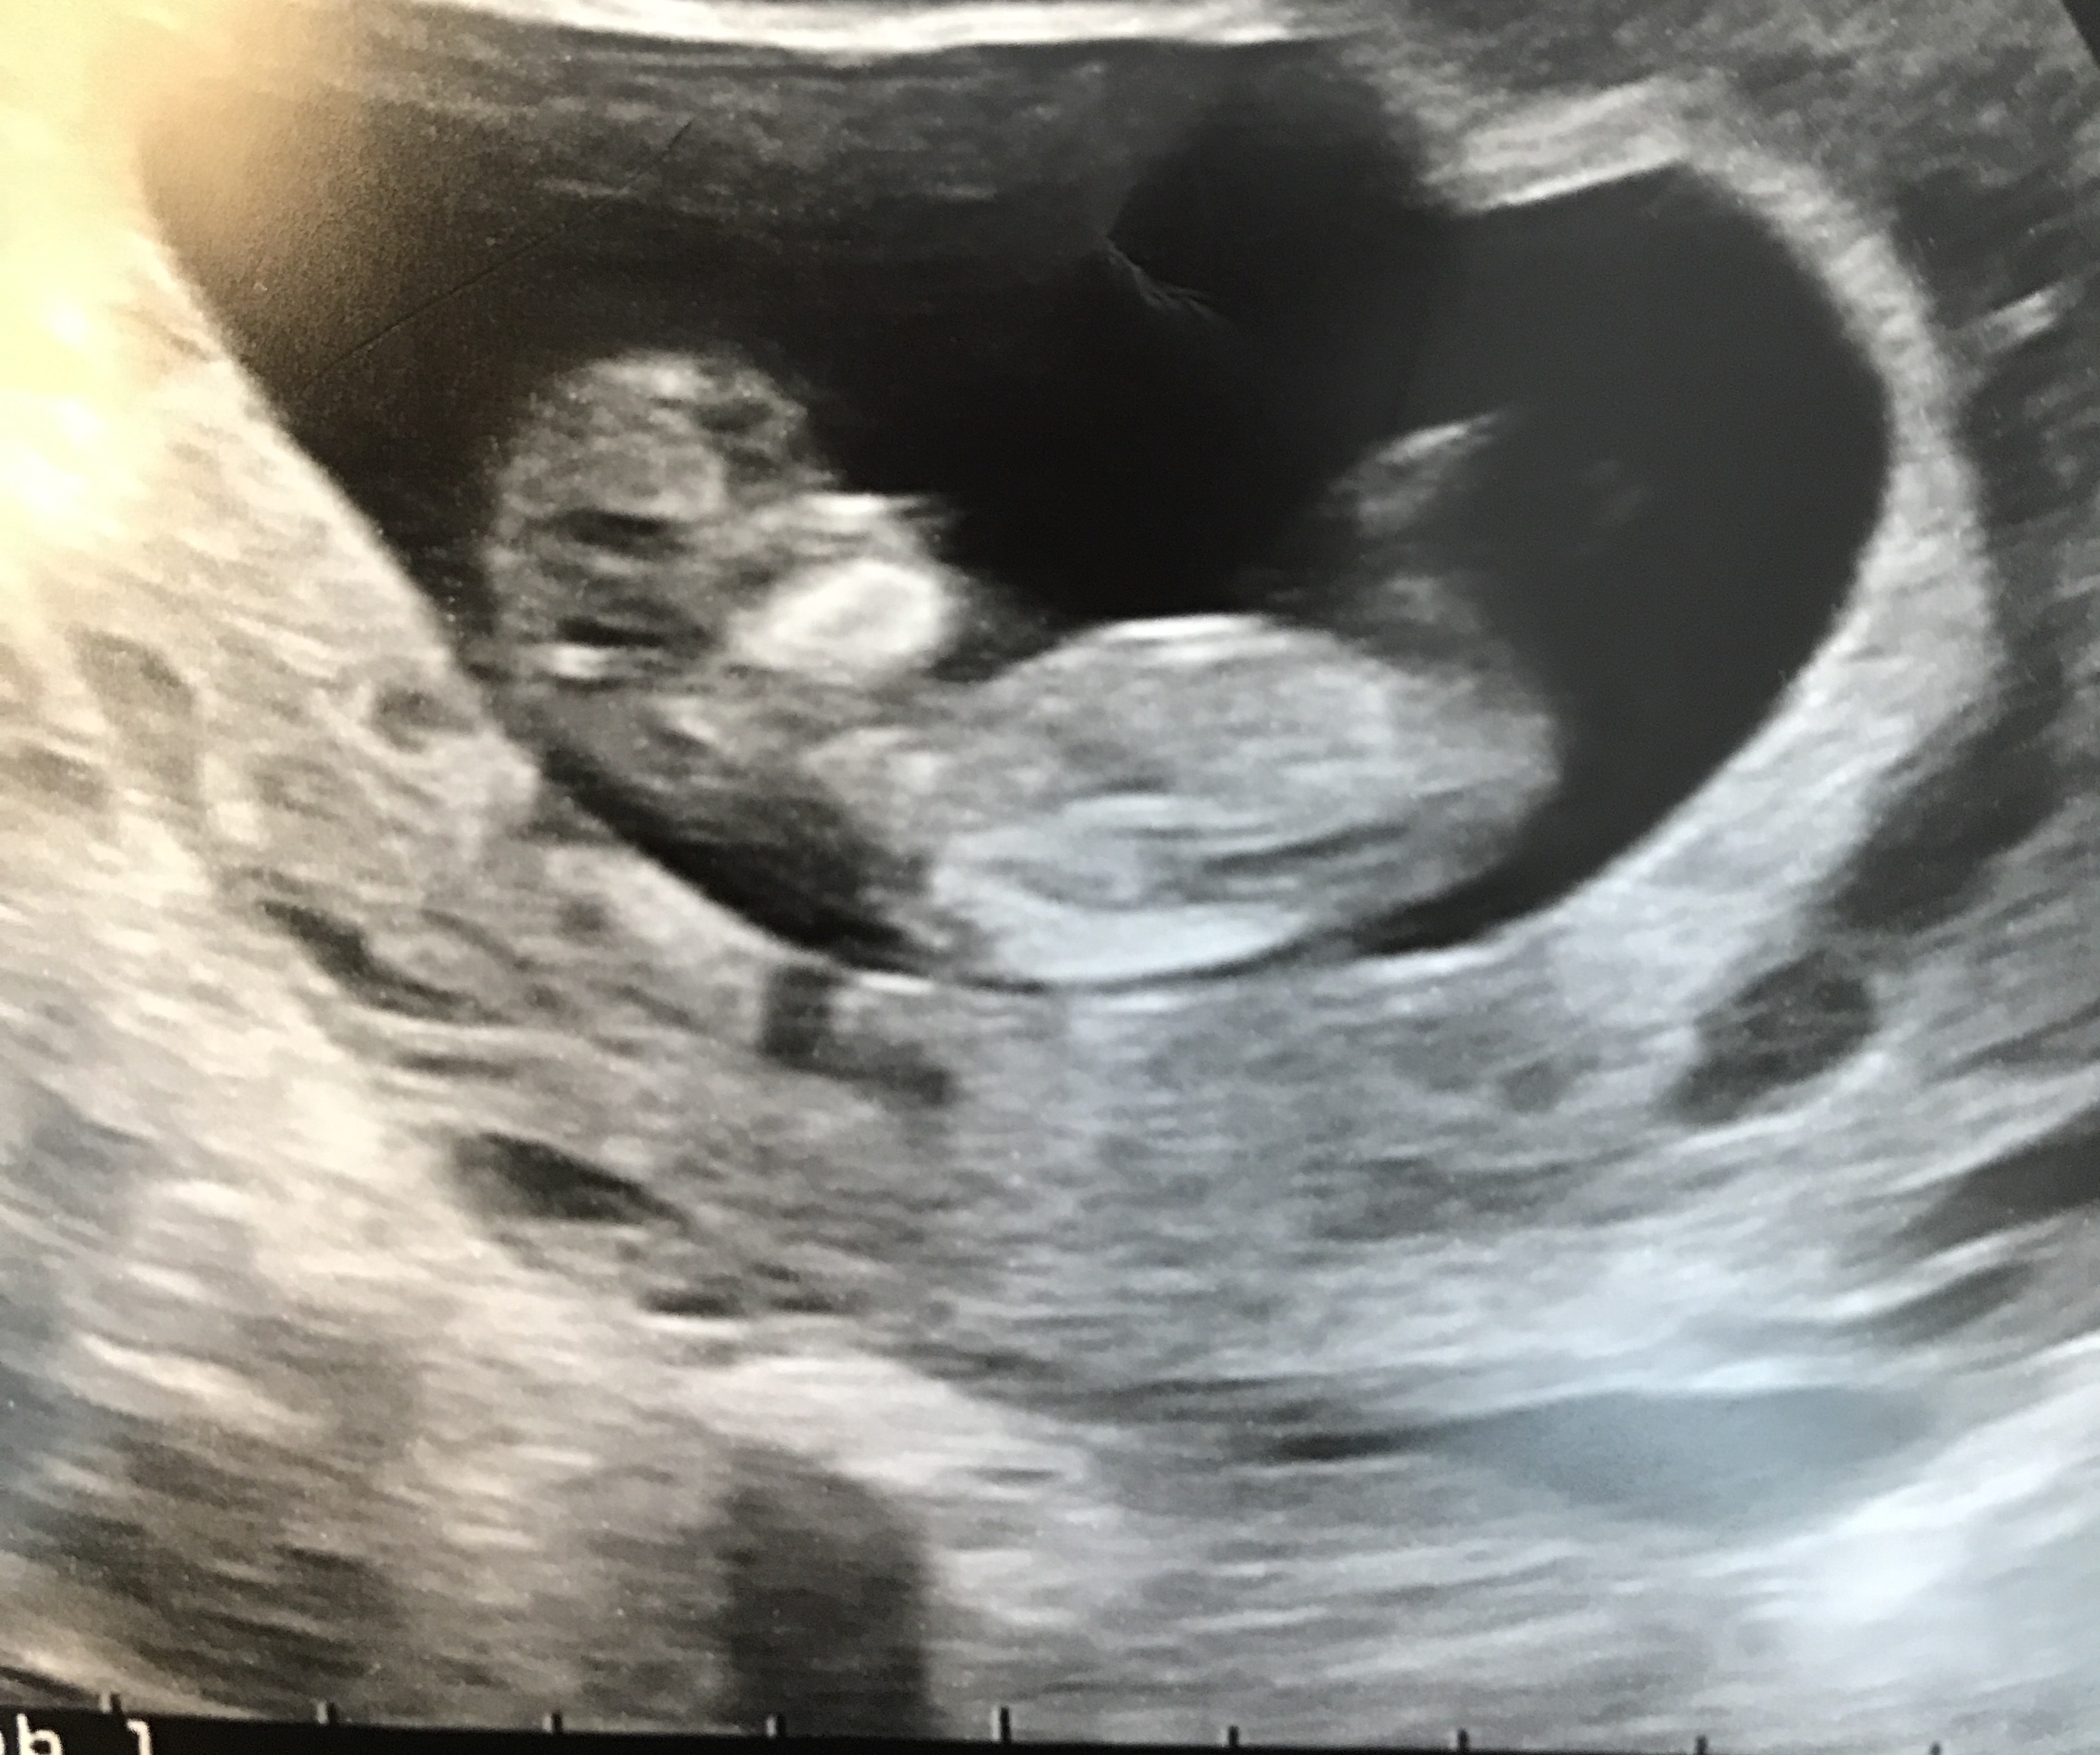

A dating scan is usually done to check how many weeks' pregnant you are, but can be done for other reasons, such as if you have had bleeding during your pregnancy or you have had previous miscarriages . If you choose to have a dating scan , it will most probably be your first scan . You will need to get a referral from your doctor or midwife for a dating scan . Most women can instead have their first scan at 11 to 13 weeks β this is usually called the 12- week scan .

If you're pregnant in England you'll be offered an ultrasound scan at around 10 to 14 weeks of pregnancy . This is called the dating scan . It's used to see how far along in your pregnancy you are and check your baby's development . The scan may also be part of a screening test for Down's syndrome . Your midwife or doctor will book you a dating scan appointment . It will usually take place at your local hospital ultrasound department .

A dating scan is an ultrasound scan carried out at around 12 weeks of pregnancy, that's used to work out your due date . It's likely to be the first time you see your baby and hear their heartbeat . This scan is also used to check that your baby's development is on track and is often part of combined screening for genetic variations, such as . . .